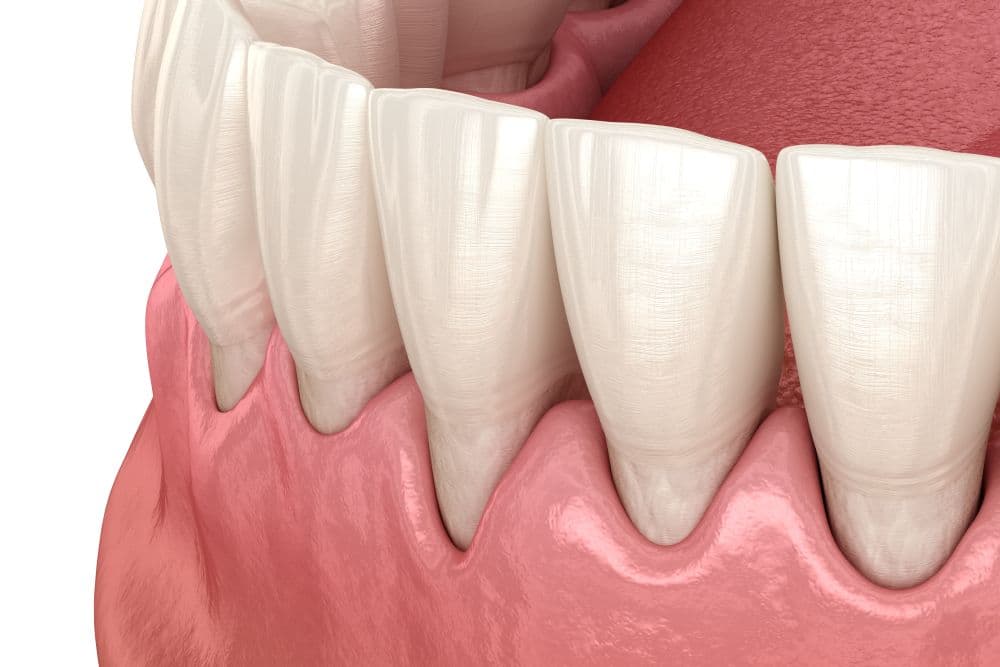

In het geval van tandvleesontstekingen (parodontitis) zal altijd als eerst een algemeen mondonderzoek moeten worden afgenomen. Een zogenaamde parodontiumstatus wordt opgemaakt. Ook wordt naar uw algehele gezondheid, levensstijl en medicatie gekeken. Bij het opmaken van de parodontiumstatus worden onder meer gegevens vastgelegd als de diepte van alle pockets, de mate van terugtrekkend tandvlees, optredende bloedingen en beweeglijkheid van tanden en kiezen. Tevens wordt een indruk verkregen van het niveau van de mondhygiëne.